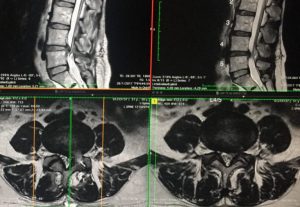

This is a question many patients often ask after knowing that their intervertebral disc herniated again. 50-year-old Ms. Li is a housewife. In May 2016, she developed low back and leg pain after bending over to take a heavy object. After an MRI scan, it was found that the lumbar intervertebral discs of the 4th and 5th segments of the lumbar spine protruded 0.7 cm to the left (see Figure 1) indenting the left side nerve root. What to do if the intervertebral disc herniated again?

But because Ms. Li’s case of herniated disc has been treated with conservative physiotherapy for six months, and she has left foot weakness and frequent urination at night. She decided to perform an MRI to confirm the situation. From the MRI film taken that day, it was found that her lumbar intervertebral discs in the 4th and 5th segments had herniated by 0.9 cm, and the compression on the cauda equina was even worse than before (see Figure 2). And she has neurological deficit condition, so it is recommended that she should undergo surgery to remove the herniated disc. Ms. Li underwent minimally invasive surgery to remove herniated intervertebral discs on January 15, 2017. After the operation, her previous low back pain and leg weakness were greatly improved.